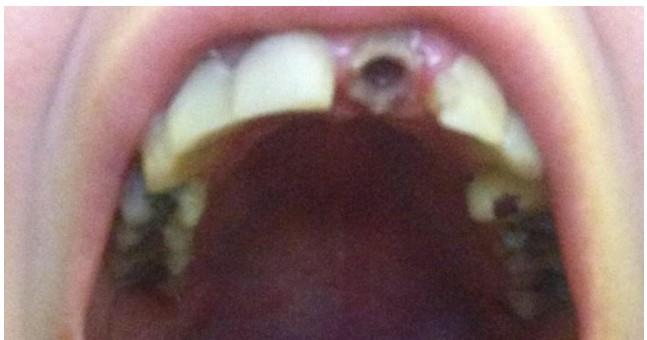

18-godišnja Linzi Grant iz Milton Kejna, veruje da misteriozno stanje uzrokuje da se njeni zubi krune i otpadaju uzrokujući jako bolne apscese.

Ovo je jako bolno za nju. Već tri zuba su joj trajno ispala. U ovom trenutku, ona nosi privremene navlake i može da jede samo mekanu hranu.

Vrlo je ponižavajuće za nju da svaki put kada kine ispadaju delovi zuba.

Doktori veruju da je problem jer ona ima dijabetes tipa 1, zbog čega se povećava rizik od dentalnih problema. Linzi oseća bol u korenu zuba, a uvek je vodila računa o zubima i ishrani.